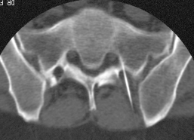

Die bisherige Therapie konnte keine stabile Ausheilung der Erkrankung bewirken. Aus diesem Grund ist die Durchführung einer Serie von zunächst 4-6 CT-gestützten Interventionen an der Wirbelsäule geplant. Mit der periradikulären Therapie bieten wir Ihnen ein modernes und erprobtes Verfahren zur Schmerztherapie im Wirbelsäulenbereich an. Dabei wird unter computertomo- graphischer Kontrolle eine dünne Nadel unter lokaler Betäubung bis unmittelbar an bzw. in den zu therapierenden Bereich vorgeschoben.

Die Computertomographie ist in der Lage, exakt Nerven, Blutgefäße und andere Körpergewebe darzustellen. Für die periradikuläre Therapie bedeutet dies erhöhte Sicherheit und die Gewährleistung einer hohen Präzision bei jeder Behandlung. Auch die zur Therapie eingesetzten Instrumente sind exakt im Bild zu erkennen und zu kontrollieren. Dadurch gelingt es, präzise Medikamente um den geschädigten Nerven bzw. in das Wirbelgelenk zu applizieren.